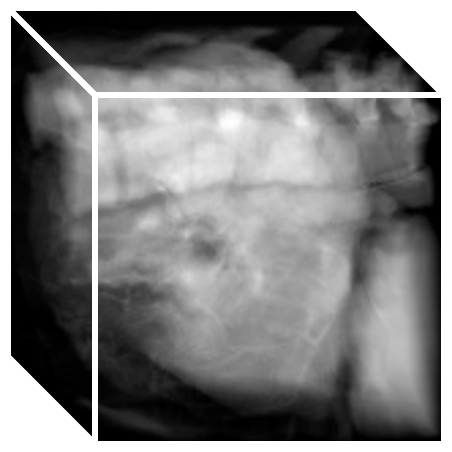

Refer to caption

(a)

(b)

(c)

(d)

(e)

(f)

(g)

(h)

(i)

(j)

(k)

(l)

(m)

(n)

(o)

(p)

(q)

(r)

(s)

(t)

(u)

(v)

(w)

(x)

(c) 2.06

(d) 0.9414

(e) 2.10

(f) 0.9408

(g) 2.46

(h) 0.9211

(i) 2.18

(j) 0.9439

(k) 2.27

(l) 0.9345

Figure 8: Example comparison among VTN ADD (c/d), VTN DD(e/f), Elastix (g/h), ANTs (i/j) and VoxelMorph-2(k/l). The input images to methods with “” are affinely aligned to a fixed atlas by ANTs and their warped images are transformed backwards according to the affine transformation aligning the fixed image and the atlas for sensible comparison. Columning and coloring are the same as those in Figure 6, except that the fixed image and the moving image are a pair of MR brain scans and that the landmarks are L7, L12 and L15. Best viewed in color.